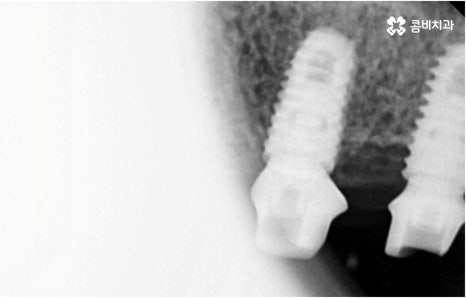

자연 치아를 살리기 위한 거의 마지막 단계의 보존 치료가 바로 신경치료, 재신경치료, 치근단절제술 등이며, 만약 치아재식술을 통해서도 살릴 수 없을 정도로 손상이 깊고 심하다면 해당 치아를 발치하고 임플란트를 통해 인공 치아로 대체해 줄 필요가 있습니다.

임플란트는 유치, 영구치 이후로 제 3의 치아라고 불리울 만큼 자연 치아의 상실에 대처하는 인공 치아 중에 가장 각광을 받고 있습니다. 저작력 회복이 80%에 가깝고 심미적으로 자신의 치아와 거의 다름없어 보이는 부분에서도 만족도가 높아 많은 분들이 찾고 있지만 식립 성공률과 안정적인 지속률에 크게 영향을 주는 올바른 위치 및 각도로의 식립을 무리하지 않게 진행하기 위해 술자의 높은 숙련도를 요하는 고난도의 수술이기 때문에 임상 경험이 많고 뛰어난 노하우를 갖추고 있는 담당의 선생님과 함께 하시는 것이 중요한 포인트라고 할 수 있어요.

환자분들의 상황에 따라 하루 만에 식립 및 임시 치아 장착까지 끝나서 바로 식사를 할 수 있는 원데이 임플란트 과정, 정밀 검사 후 디지털 장비를 이용하여 모의 수술 후 맞춤 가이드를 따라 무절개 / 최소절개 수술을 진행하는 네비게이션 임플란트 과정 등 관련 기술이 점점 더 섬세하게 발달하고 있어서 보다 편안한 이용이 가능하게 된 것은 사실이지만 본래 자신의 치아보다 좋은 인공 치아는 없을 것이기 때문에 건강할 때 이를 잘 유지 관리하고 구강 질환이 발생했을 때는 되도록 빠르게 이에 대처하실 필요가 있어요.